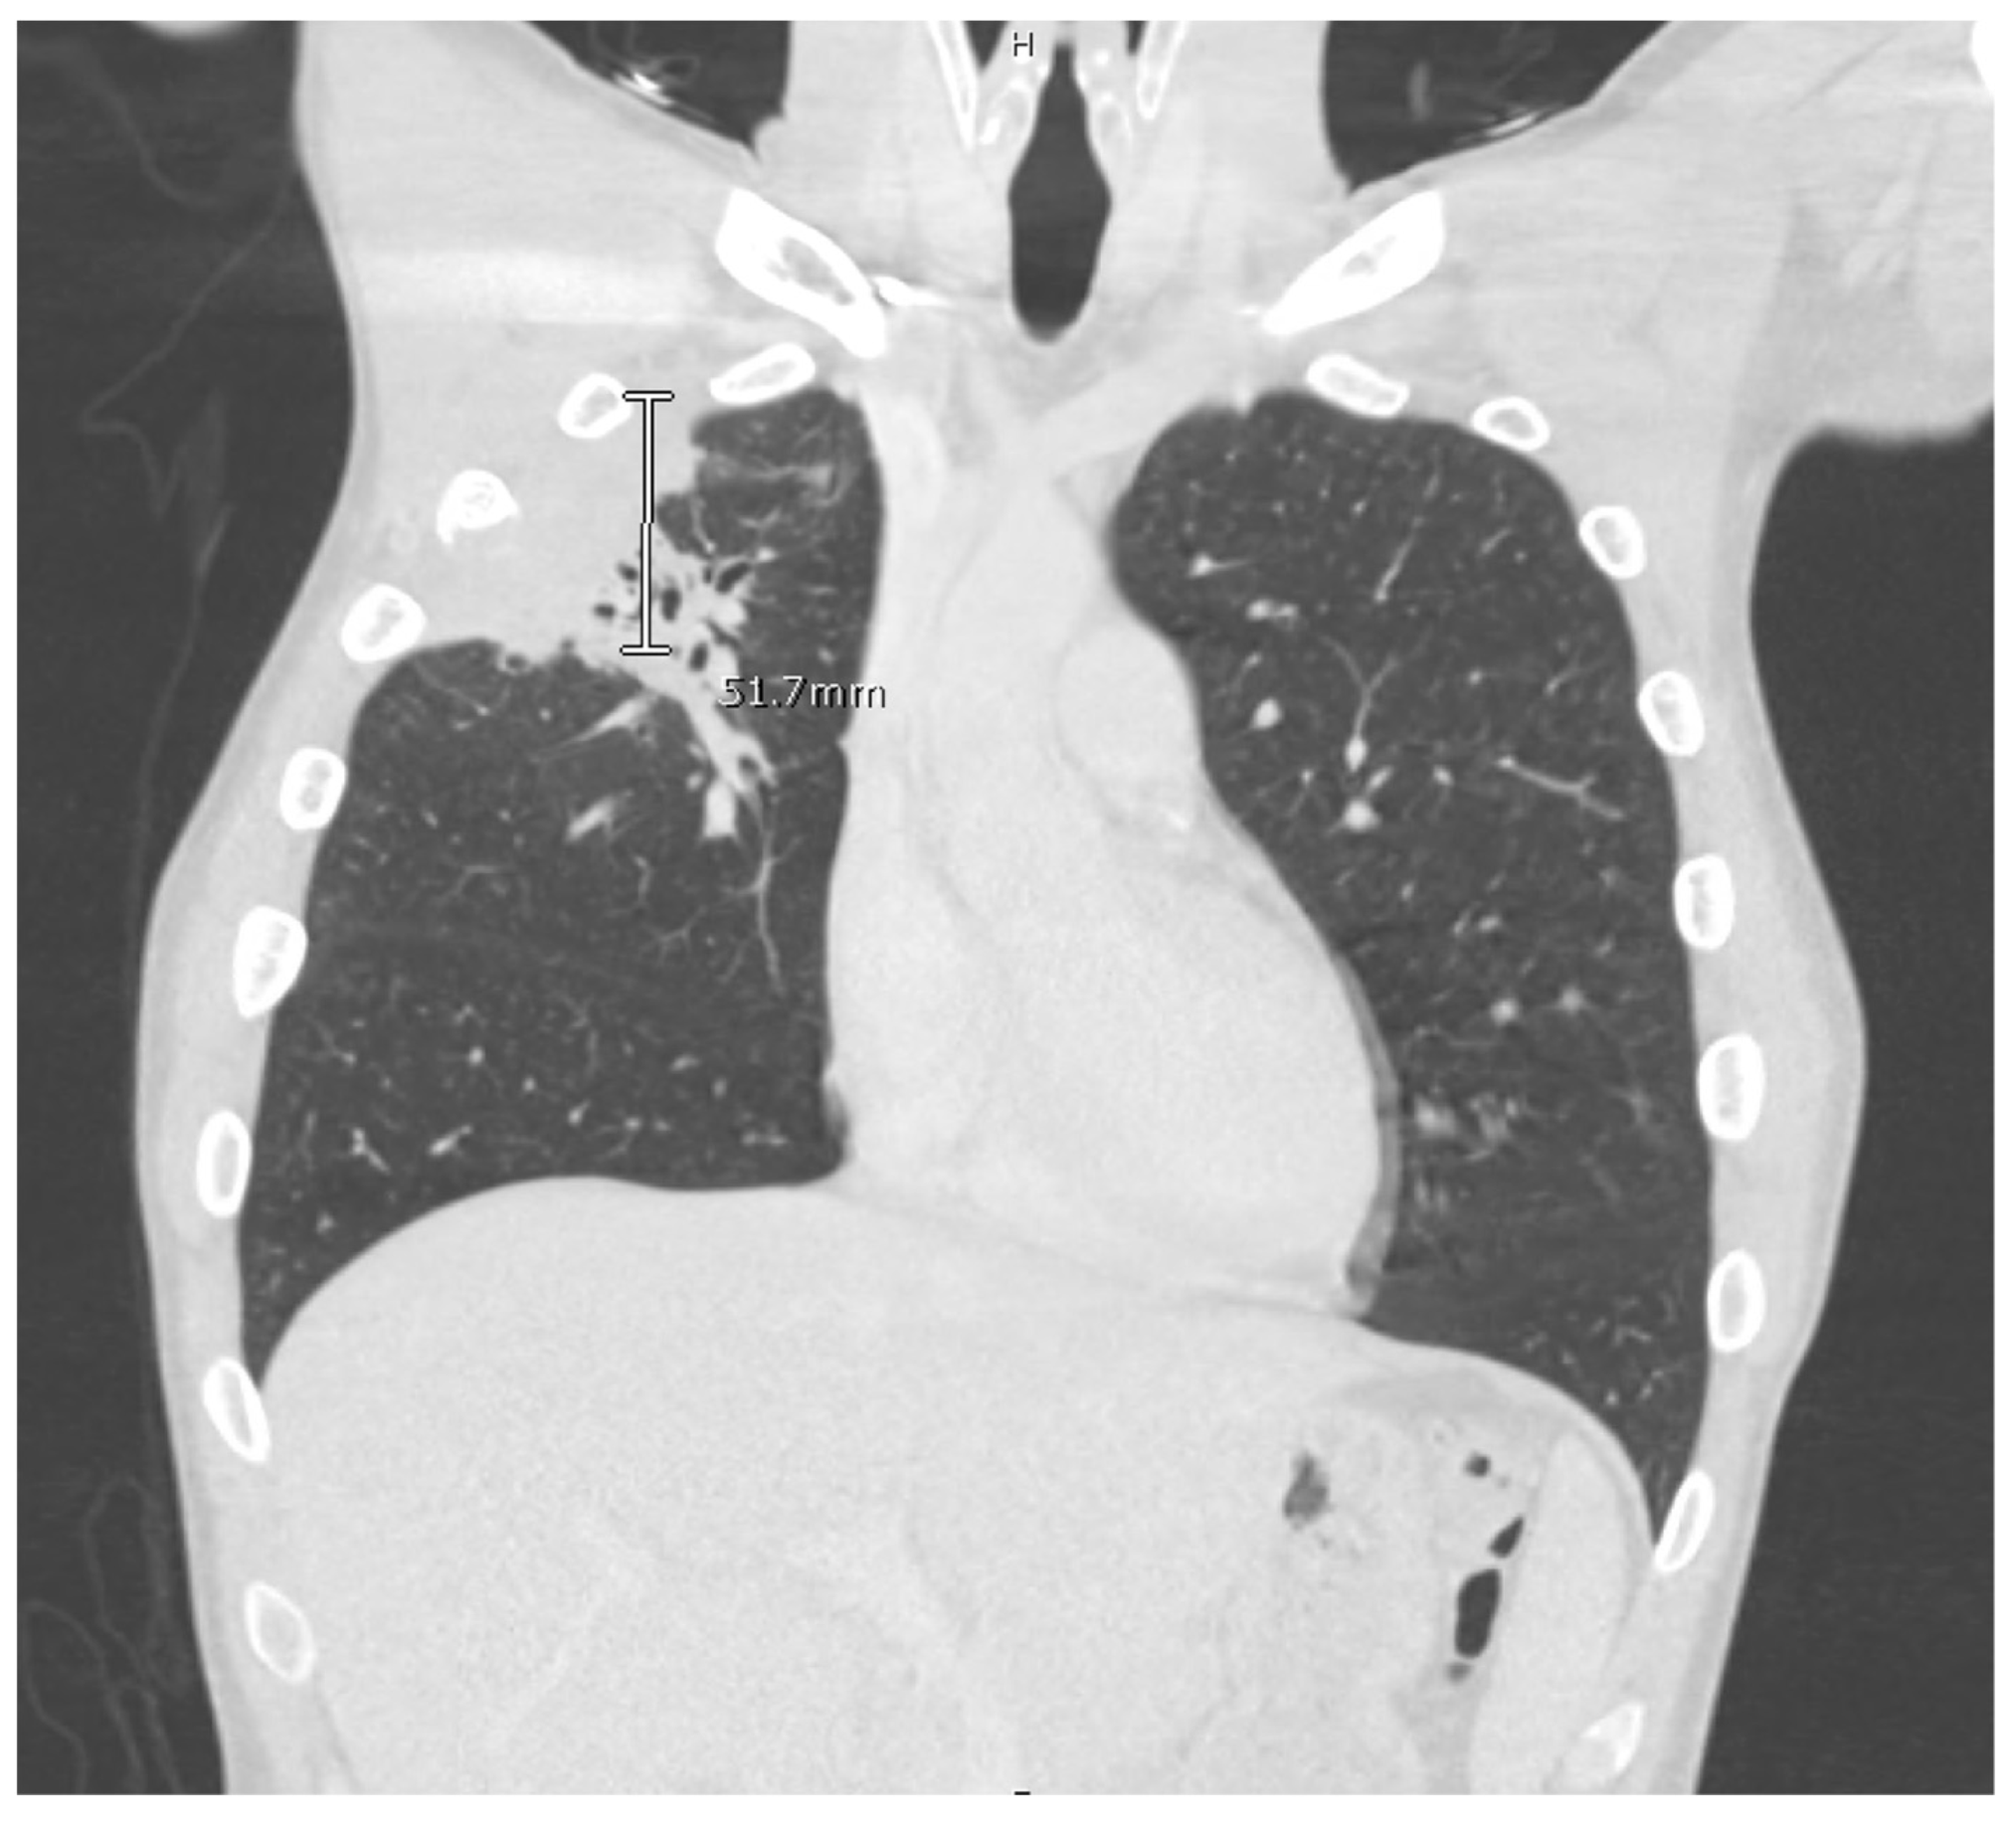

Blastomycosis Dog Chest X Ray . the clinical spectrum of pulmonary blastomycosis is diverse, ranging from. A miliary nodular pattern is present. blastomycosis is a systemic fungal infection caused by the dimorphic fungus blastomyces dermatitidis. blastomycosis should be considered in dogs with draining cutaneous nodules and clinical signs of respiratory disease. Objective —to identify radiographic patterns in dogs with pulmonary. The infective form of the. right lateral radiograph of a dog with blastomycosis. In cats, respiratory tract involvement occurs most frequently, followed by involvement of the cns, regional lymph nodes, skin, eyes, and gi and urinary tracts.

A miliary nodular pattern is present. The infective form of the. blastomycosis is a systemic fungal infection caused by the dimorphic fungus blastomyces dermatitidis. the clinical spectrum of pulmonary blastomycosis is diverse, ranging from. Objective —to identify radiographic patterns in dogs with pulmonary. right lateral radiograph of a dog with blastomycosis. In cats, respiratory tract involvement occurs most frequently, followed by involvement of the cns, regional lymph nodes, skin, eyes, and gi and urinary tracts. blastomycosis should be considered in dogs with draining cutaneous nodules and clinical signs of respiratory disease.